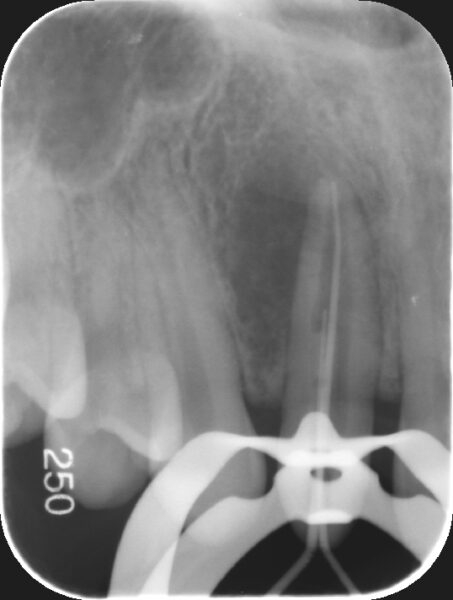

【術前レントゲン】

側方に骨欠損が認められます。(根の先の黒い部分)

歯内歯という珍しい形態を示しています。

CTでも同様に骨欠損が認められ、歯内歯形態を示しています。

根の外側と内側から根管口という入り口があり、2本入っているのが分かります。また、この2本の根管は合流しており複雑な形態を示していることが分かります。

2本の根管に緊密に根管充填材(MTA)が充填出来ていることが確認できました。

術後3か月後のレントゲンでは黒くなっていた部分が回復してきており、骨が再生してきていることが認められました。